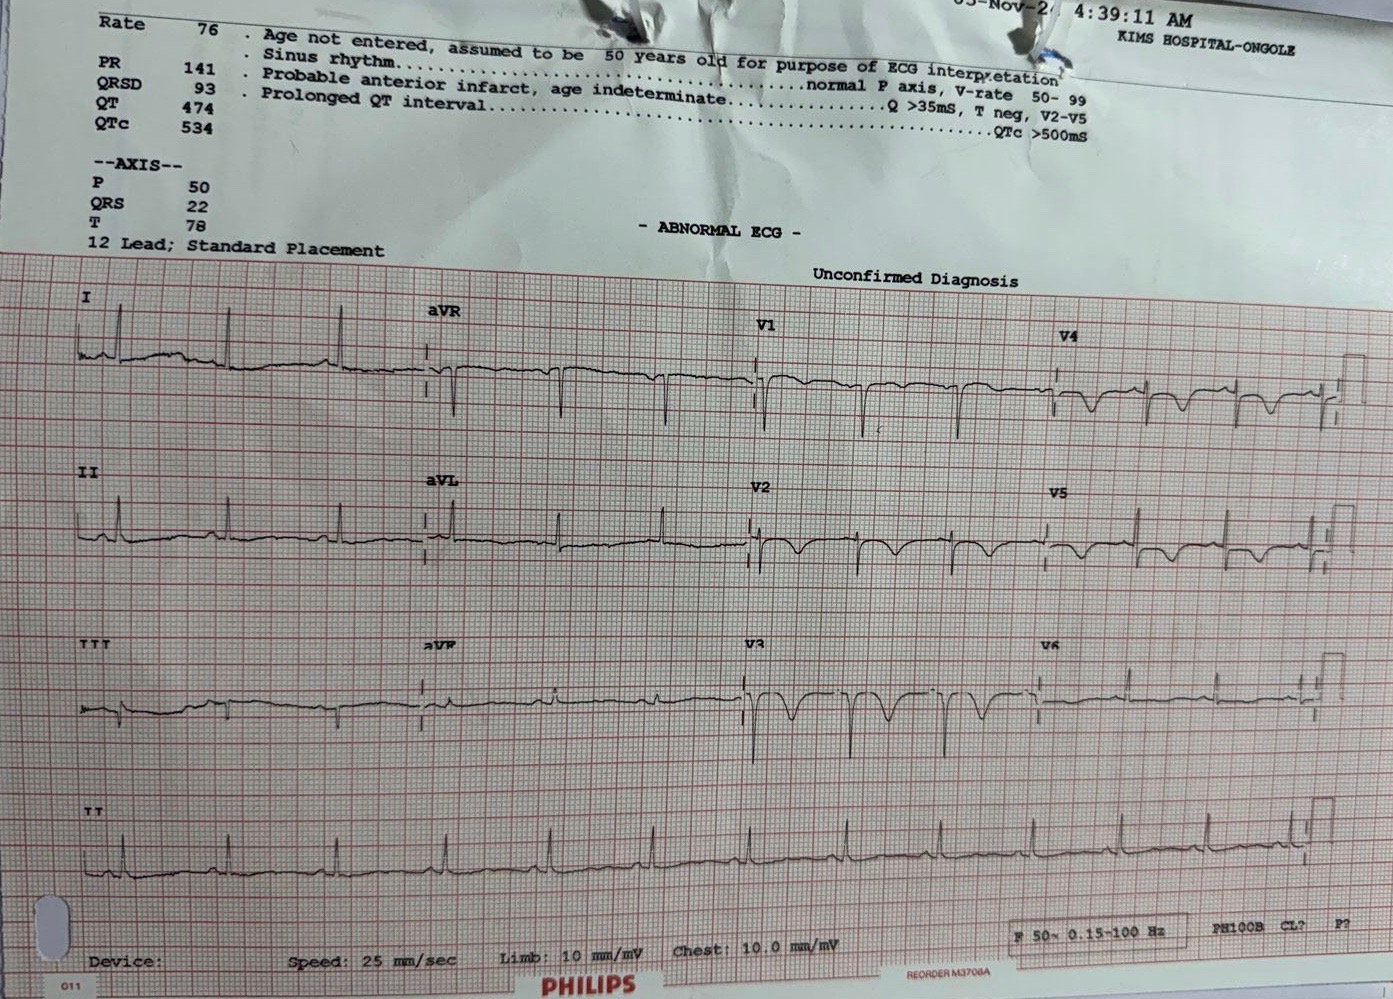

Relevant Test Results Prior to Catheterization

Troponin I was negative. ECG showed ST depressions in v1 to v4 leads with sinus rhythm. Echocardiography showed mild hypokinesia in anterior wall with mild LV dysfunction.